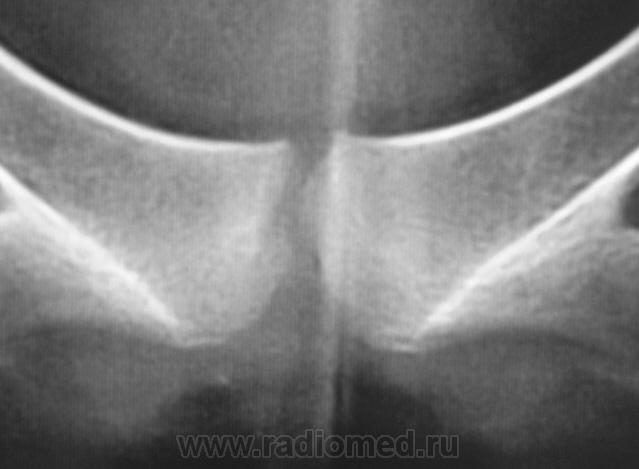

2. Лонное сочленение очевидно,подверглось значительному растяжению (имеется локальный вакуум-феномен слева), умеренно выраженые явления симфизита (опять же - постравматического).

1. По первым снимкам не отпускало впечатление о повреждении левого крестцово-подвздошного сочленения. После подготовки вроде-бы все нормально, но все равно что-то гложет.

2. А на боковой массе крестца справа разве не линия консолидирующегося перелома?

Возможно, перелом последнего копчикового тоже был?

Поздно заметил ветку.. увидел симфизит, перелом остистого L4, мазоль Co 5, и  конечно spina bifida S1 ))) глянуть бы межпозвоночные..